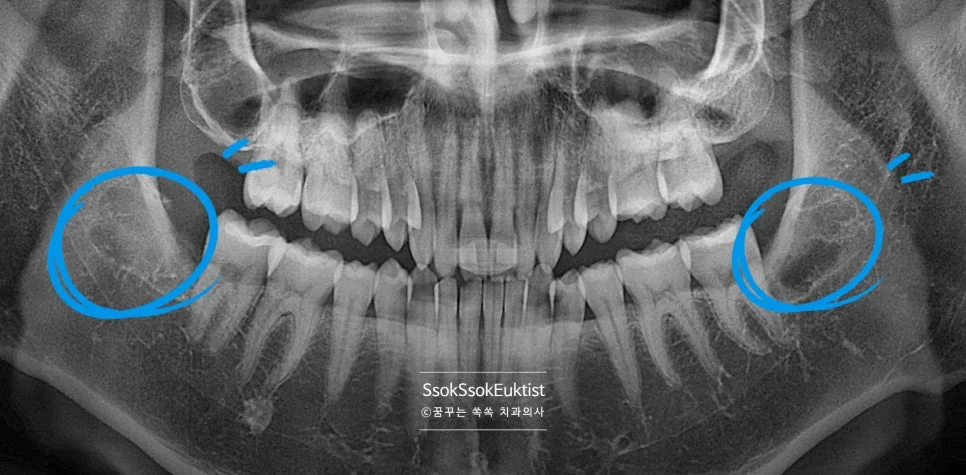

파노라마 엑스레이 — 상악과 하악 사랑니 위치 전체 확인

중간 난이도 완전 매복 사랑니 파노라마 엑스레이

잇몸 하방에 완전히 묻혀 있는 완전 매복 사랑니입니다. 사랑니가 맹출 하면서 잇몸의 통증을 호소하는데요, 뒤의 턱뼈와의 공간이 부족하여 어차피 매복될 치아라 바로 발치를 말씀드립니다.